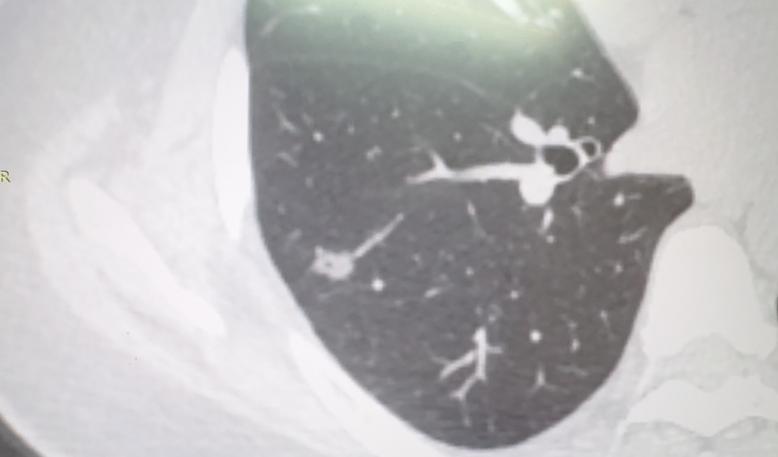

“医生,我家里还有孩子要照顾,最大的才八岁……”诊室里,一位36岁的女性患者,红着眼眶问我。 她在体检中发现了一个接近9mm的磨玻璃结节,从形态上看,需要考虑浸润癌的可能性大。结节位置靠近肺外周,手术切除是比较理想的选择。 但一提到手术,她的担忧全写在了脸上:万一手术有什么风险,孩子该怎么办? 其实,肺结节手术在胸外科领域并不算大型手术。现在大多采用胸腔镜微创技术,只需要在胸壁上开几个小孔,就能完成结节的切除。这种手术创伤小、出血少,术后恢复也快,大多数人都能够耐受。 具体来说,像陈女士这种结节不大、位置又比较靠边的情况,一般只需要做肺部分切除,也就是楔形切除或者肺段切除,对肺功能的影响非常有限,手术时间也不长。 当然,如果结节再大一些、位置再深一点,可能就需要做肺叶切除,那手术范围和难度会相应增加。不过对于经验丰富的胸外科医生来说,这类手术技术已经非常成熟,安全性是有保障的。 需要特别说明的是,如果患者年纪大、基础疾病多,我们会更谨慎地评估手术风险,有时也会考虑其他替代方案。但这位女性患者还年轻,身体底子好,术后恢复会很快。 作为医生,我们的责任不仅是治病,也要为患者的实际生活考虑!现在做手术范围小、效果好,大概率能彻底治愈。从长远来看,我觉得手术是目前最负责任的选择。 也别太焦虑,我们可以一起商量,看看在孩子照顾方面能不能提前做些安排。治病是为了更好地陪伴孩子长大,您说对吗?[玫瑰][谢谢]胸外科乔贵宾医生肺结节[超话]